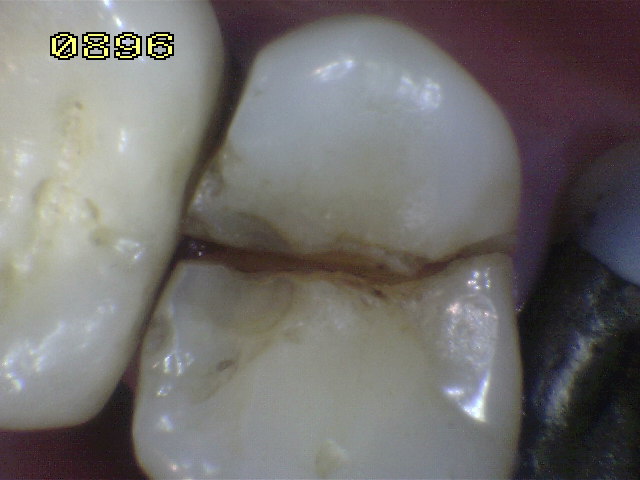

Dos conductos bien delimitados, ensanchados con limas rotatorias, recidiva de caries en distal.